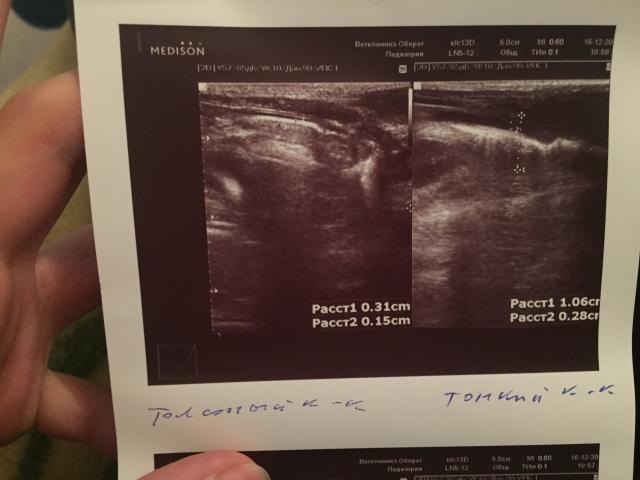

Если можно, то немного подробнее. На основании чего вам поставили такой диагноз, только на основании проведенного УЗИ? Может быть, собаке брали какие-то анализы? Если да, то выложите, пожалуйста, здесь их результаты. Если только данные УЗИ, то это разговор ни о чем (я имею ввиду панкреатит). Гастрит по данным УЗИ вообще не ставят.

Поставили диагноз на основании УЗИ , а до этого сдавали кровь

К сожалению, ничего не могу рассмотреть. Попробуйте сами прочесть описание с фото. Если сможете, сделайте снимок более качественным. Или можно снять крупнее по частям. Может быть, тогда буквы будут видны более четко.

Спасибо, фотографии четкие. Я все прочитал. Как я и думал, там и "не пахнет" никаким гастродуоденитом, а тем более, панкреатитом.